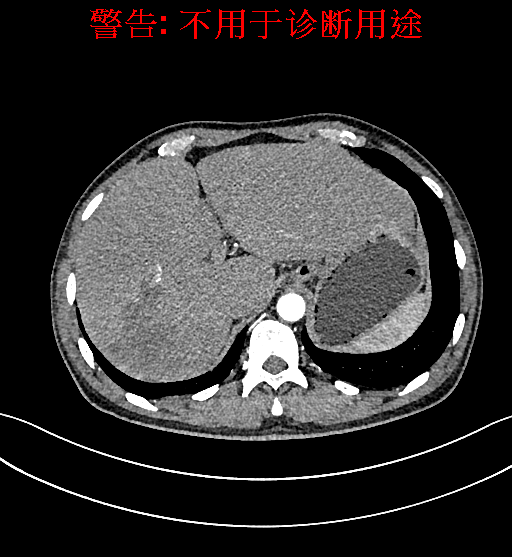

上腹部增强CT示肝右叶多发低密度结节、片团影伴肝门区、肝胃间隙多发肿大淋巴结,原发性肝Ca可能性大,请结合临床肝硬化肝脏小囊肿。

术前CT检查: